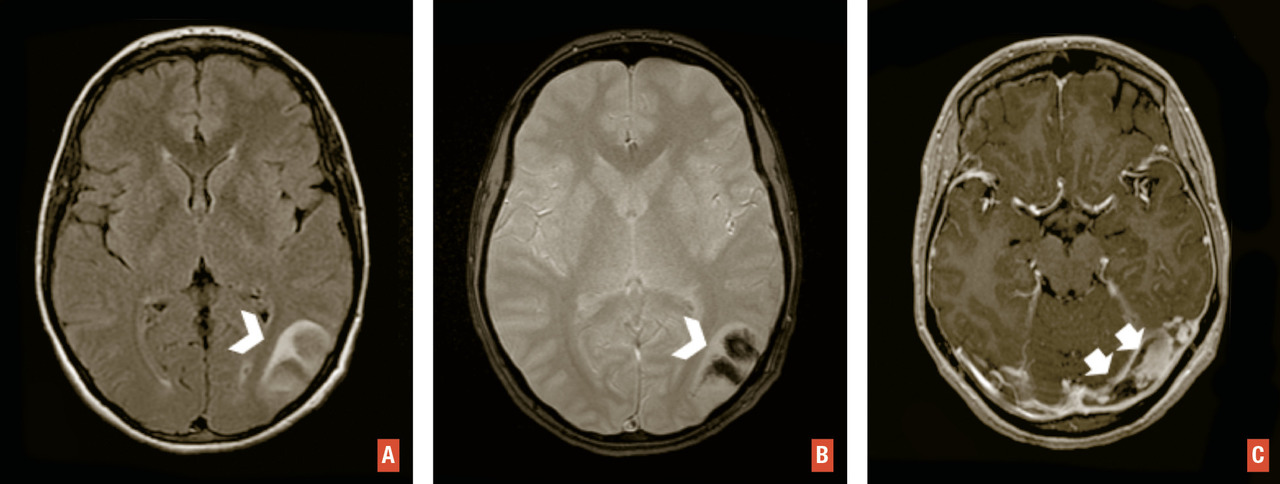

En IRM, le bilan comporte des séquences injectées dynamiques, une séquence de susceptibilité magnétique et une séquence volumique T1 sans et avec injection de gadolinium. L’injection dynamique permet une visualisation précoce des structures veineuses en cas de fistule ou de malformation artérioveineuse. Ce bilan peut être complété par une artériographie cérébrale en cas d’hématome lobaire non traumatique sans cause retrouvée en IRM. La séquence 3D T1 avec injection de gadolinium cherche à éliminer une tumeur sous-jacente et à s’assurer de la perméabilité des sinus veineux. Un thrombus veineux apparaît sous la forme d’un hyposignal linéaire sur les séquences de susceptibilité magnétique (T2* ou SWI) et d’un défaut de rehaussement d’un sinus veineux ou d’une veine corticale sur les séquences après injection (fig. 7 ). En cas d’hématome lobaire du sujet âgé, ces séquences recherchent des anomalies évocatrices d’angiopathie amyloïde telles que des microsaignements (« microbleeds ») de disposition périphérique, des séquelles d’hématomes et une sidérose corticale superficielle.

En IRM, le bilan comporte des séquences injectées dynamiques, une séquence de susceptibilité magnétique et une séquence volumique T1 sans et avec injection de gadolinium. L’injection dynamique permet une visualisation précoce des structures veineuses en cas de fistule ou de malformation artérioveineuse. Ce bilan peut être complété par une artériographie cérébrale en cas d’hématome lobaire non traumatique sans cause retrouvée en IRM. La séquence 3D T1 avec injection de gadolinium cherche à éliminer une tumeur sous-jacente et à s’assurer de la perméabilité des sinus veineux. Un thrombus veineux apparaît sous la forme d’un hyposignal linéaire sur les séquences de susceptibilité magnétique (T2* ou SWI) et d’un défaut de rehaussement d’un sinus veineux ou d’une veine corticale sur les séquences après injection (